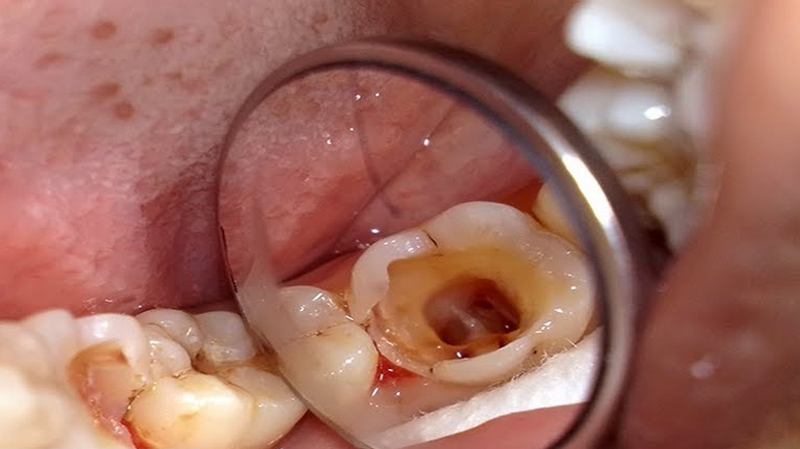

Viêm quanh cuống răng có thể do vi khuẩn từ mô xung quanh răng xâm nhập vào vùng cuống răng, gây ra tình trạng viêm nhiễm. Ngoài ra, viêm tủy răng cũng có thể là nguyên nhân dẫn đến tình trạng viêm quanh cuống răng do tủy bị hoại tử. Viêm tủy thường do vi khuẩn xâm nhập từ lỗ sâu, giải phóng một loạt các chất độc hại của vi khuẩn vào mô xung quanh cuống răng, bao gồm:

Viêm quanh cuống mạn thường gặp ở những người có tiền sử bị viêm tủy hoặc áp xe quanh cuống cấp tính. Biểu hiện thường thấy là răng bị đổi màu, vùng ngách lợi quanh cuống răng sưng nhẹ. Chụp X-quang có thể phát hiện tình trạng tiêu xương ổ răng.